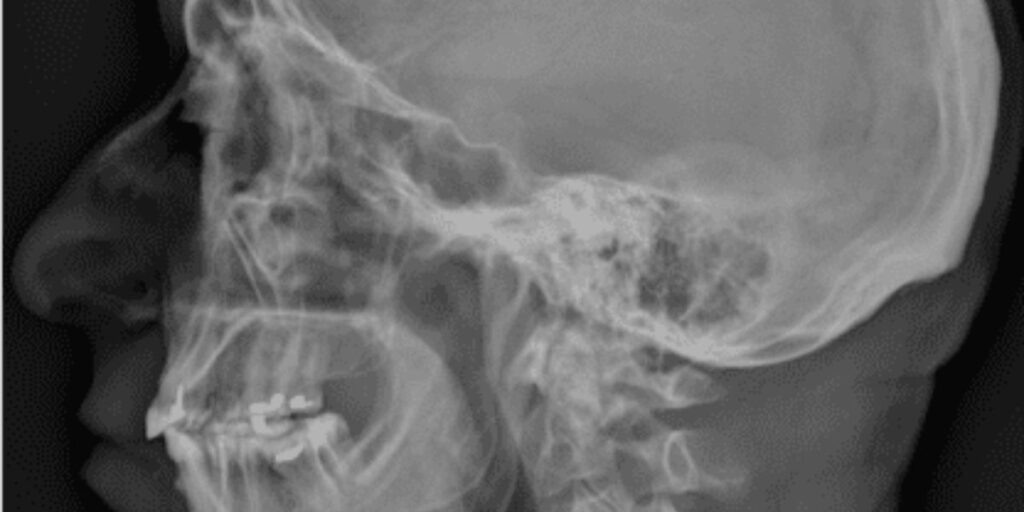

L’abbreviazione RX si riferisce alla radiografia, un metodo di imaging medico che utilizza radiazioni ionizzanti per creare immagini dettagliate delle strutture ossee e dei tessuti interni. L’RX Ossa Nasali si focalizza sulle ossa del naso, fornendo un’immagine chiara e nitida che consente di visualizzare eventuali alterazioni.

L’RX Ossa Nasali è un esame non invasivo che viene effettuato presso il Poliambulatorio S-Medical Group di Sora e si avvale di una quantità minima di radiazioni per ottenere immagini delle ossa nasali. Questo esame è particolarmente utile per individuare lesioni traumatiche, come fratture o dislocazioni, nonché per valutare deviazioni del setto nasale, sinusiti croniche o la presenza di polipi.

Cosa si Osserva con un RX Ossa Nasali?

L’RX Ossa Nasali permette di visualizzare chiaramente le ossa del naso e le loro eventuali anomalie strutturali. Questo esame risulta particolarmente efficace per:

• Identificare Fratture: L’RX evidenzia eventuali linee di frattura e scomposizioni ossee.

• Valutare il Setto Nasale: Consente di osservare deviazioni che potrebbero ostacolare la respirazione corretta.

• Diagnosticare Sinusiti: Rileva accumuli di liquidi o infiammazioni nei seni nasali.

• Individuare Polipi o Masse: Consente di osservare la presenza di eventuali formazioni anomale.